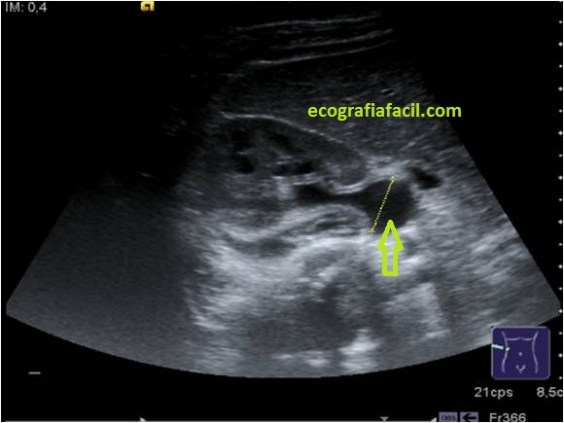

Las Hidronefrosis se pueden presentar en casos leves, como este:

In the image above you can see a Kidney where the cortex and the renal sinus are clearly differentiated, the Calyllic Champs are observed … Hydronephrosis can occur in mild cases, such as this:

Donde encontramos un «pelvis extrarrenal», anecoica, grande en la salida del riñón hacia el Uréter…El parénquima renal está prácticamente conservado, casi normal o normal…Pero en extremos graves, como la hidronefrosis de III-IV grado encontramos estas imágenes:

Where we find an «extrarenal pelvis», anechoic, large at the exit of the kidney to the ureter … The renal parenchyma is practically preserved, almost normal or normal … But in severe extremes, such as hydronephrosis of III-IV degree we find these images: